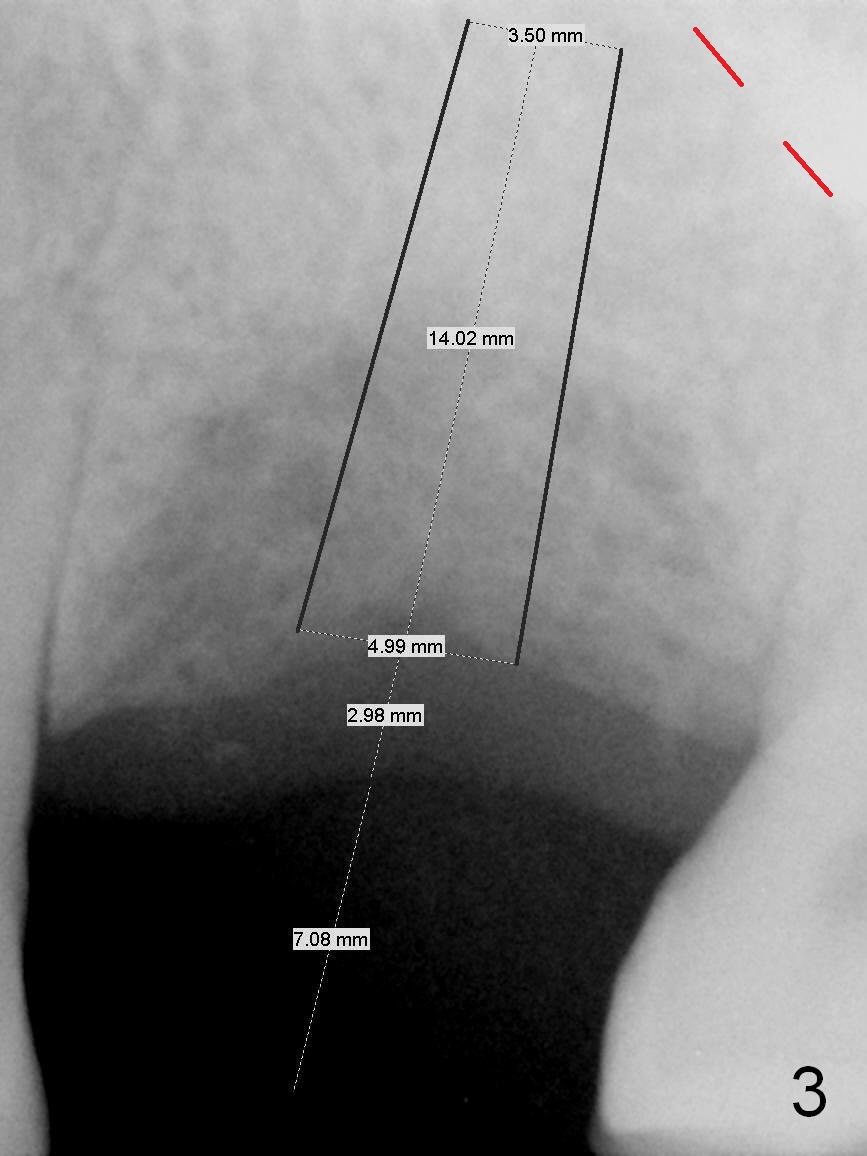

The tooth #14 of a 52-year-old lady had severe bone resorption 6 years ago (Fig.1 (red dashed line: sinus floor)). The bone resorption persists after the tooth exfoliated (Fig.2). Clinically, the buccal plate (Fig.4 (occlusal view) upper panel: B) is concave (take preop photos). #15 scalpel will be used for incision (red line in Fig.4 lower panel, near the lingual plate (L)) and initiation of bone expansion. The latter is followed by bone scalpels, bone blades and RTs at the depth of 14 mm. A 4.5x17 mm Tatum tapered tap is used for 14 mm. PA is taken. If the bone is dense, the depth is less than 14 mm in bone. Use RT2,3 to reach 17 mm. A 5x14 mm bone-level implant is placed (Fig.3). Crown cementation will be done for the tooth #3 before surgery.